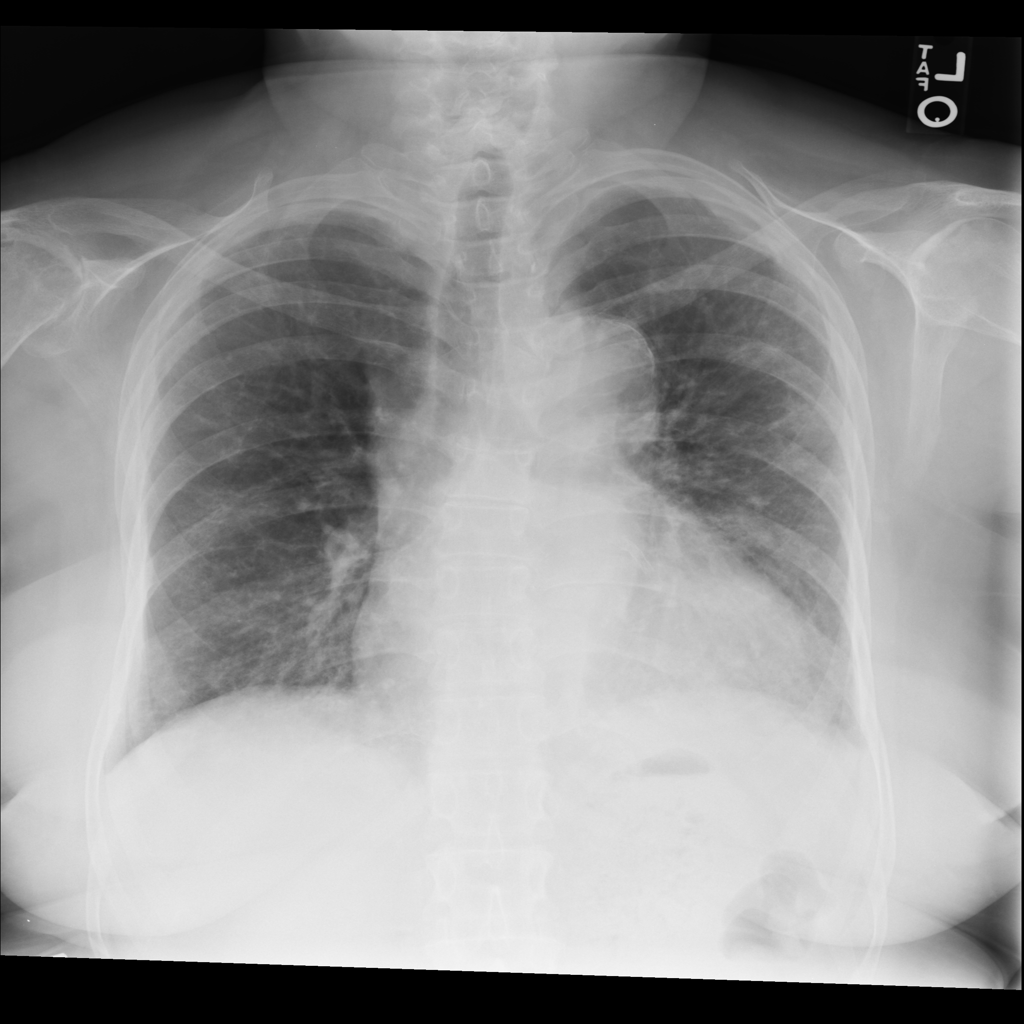

PAT-40F9 · IMG-004Effusion

PAT-40F9 · IMG-004

PA